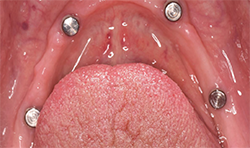

The patient’s medical history was evaluated for a mandibular fixed hybrid prosthesis using four Bicon implants and a TRINIA substructure. A CBCT revealed adequate bone for implantation and reviewed clinically after properly dissecting the mental nerve to avoid paresthesia. Four implants were placed through the anterior to increase the AP spread. Mandibular full thickness mucoperiosteal flap across the ridge was released and mental foramen were identified bilaterally. The posterior implant was placed 5 mm anterior to the mental foramen. All sites were prepared, checked for parallelism and enlarged to receive four implants each 4 mm x 8 mm with a 2.5 well (Fig. 4).

After normal healing and integration, 5 x 5 mm healing abutments with 2.5 mm wells were placed. At the impression appointment, the sulcus was prepared using a sulcus reamer and a PVS impression was taken and sent to the lab. The patient was happy with the wax try-in and the lab was instructed to finish the case. Delivery was uneventful (Figs. 5, 6).